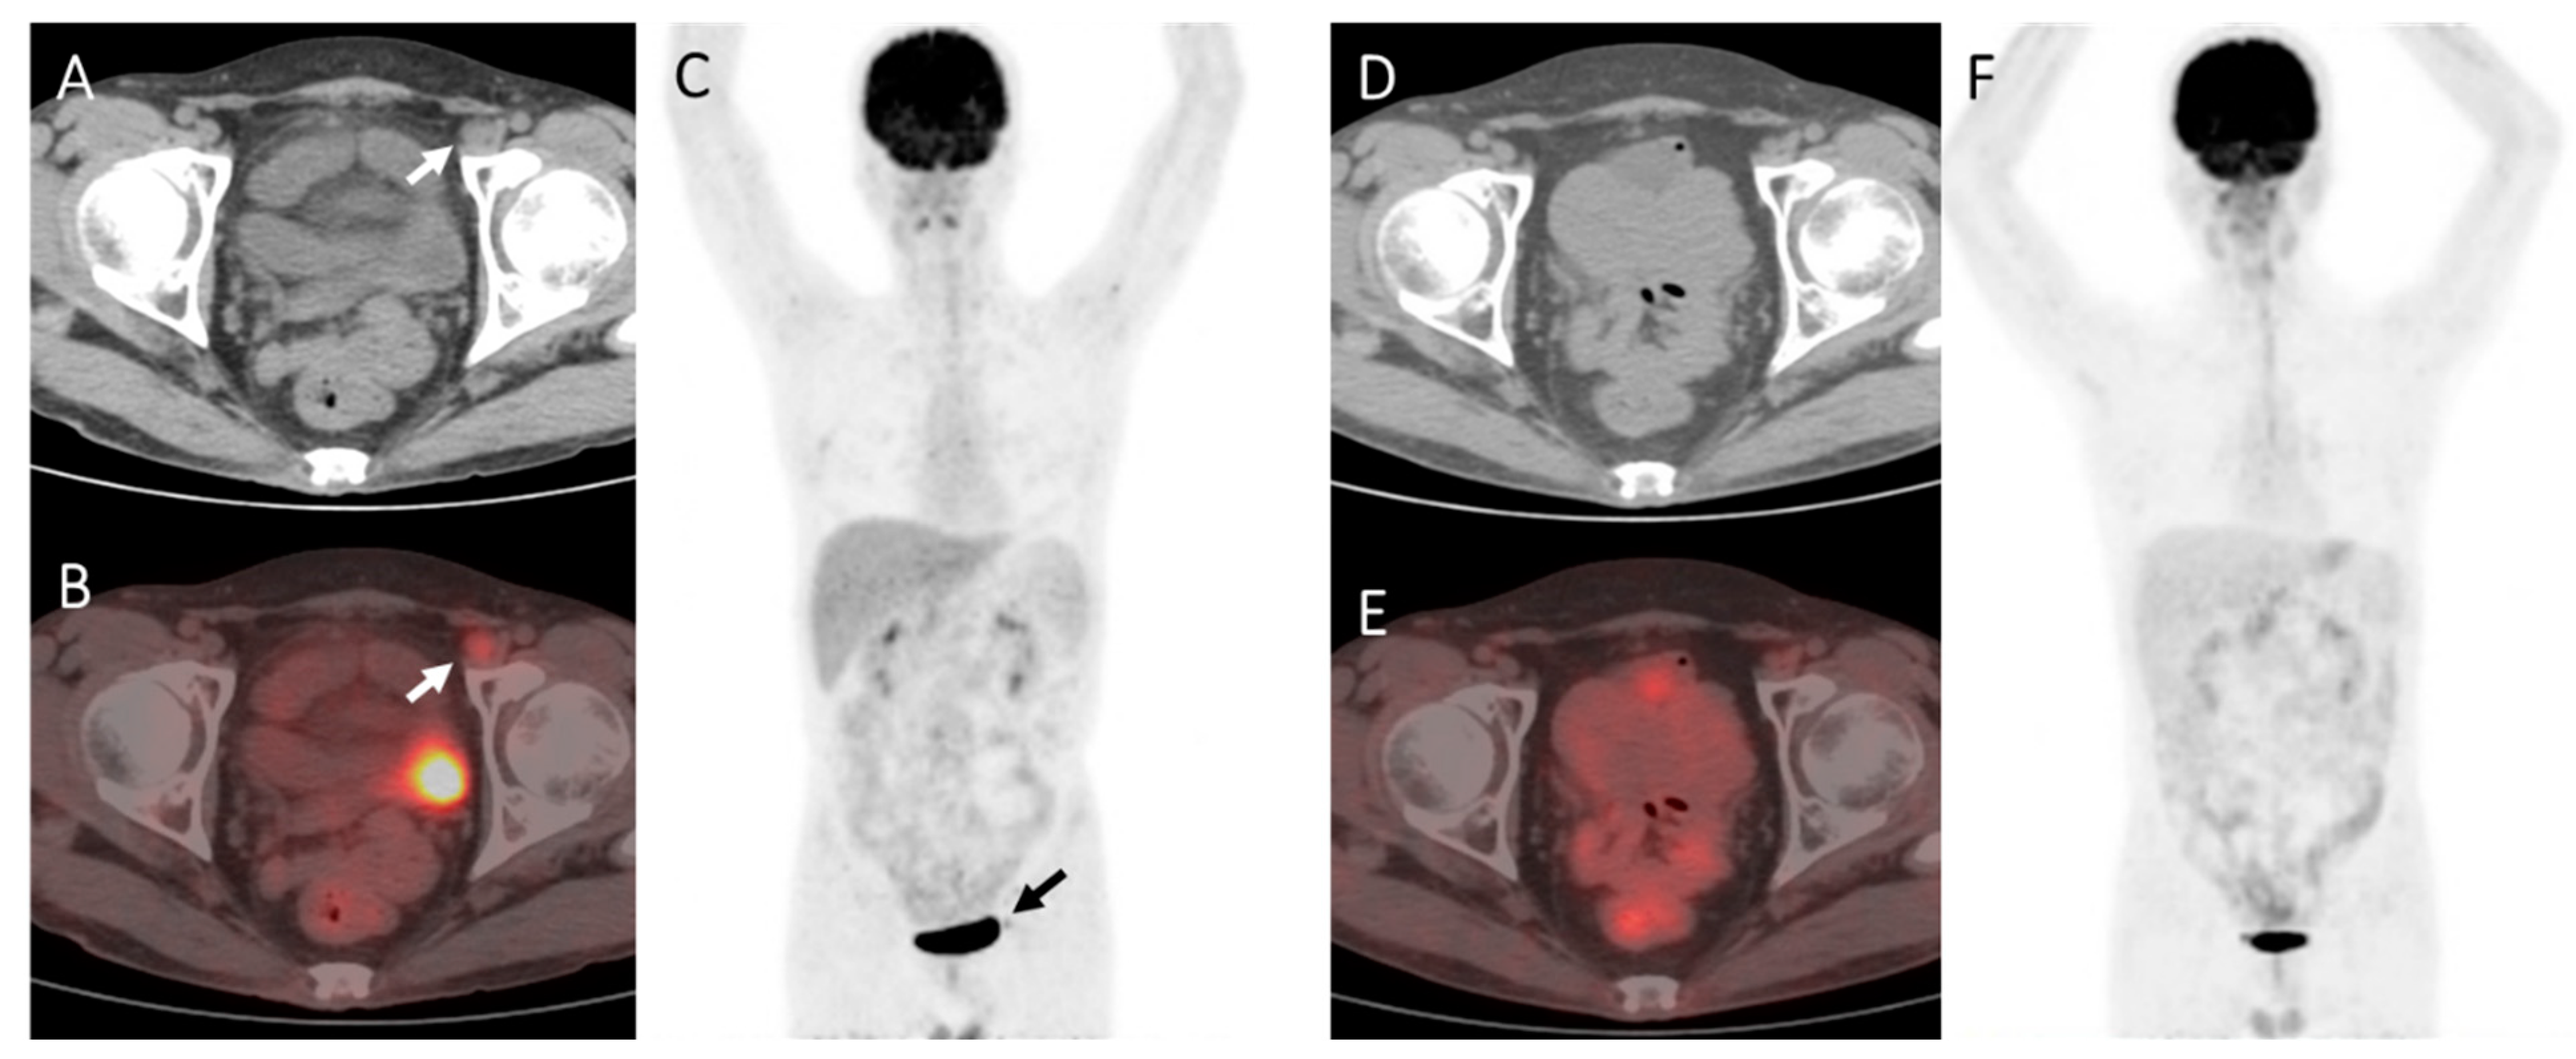

Figure 2.

A case of B-Lymphoblastic lymphoma of the pancreas and bones in a 43-year-old male. The patient was treated with chemotherapy and achieved complete remission. The patient then received allogeneic SCT and underwent 18F-FDG PET-CT 1.5 months after transplantation for assessment. (A–C): PET showed an FDG-avid pelvic lymph node (arrow), about 1.3 * 1.1 cm2 in size, SUVmax3.5 (DS = 4). (D–F): A follow-up PET imaging was carried out 3 months later with no treatment, which showed the FDG-avid foci disappeared. Therefore the post-SCT PET at 1.5 months was determined as a false positive result.